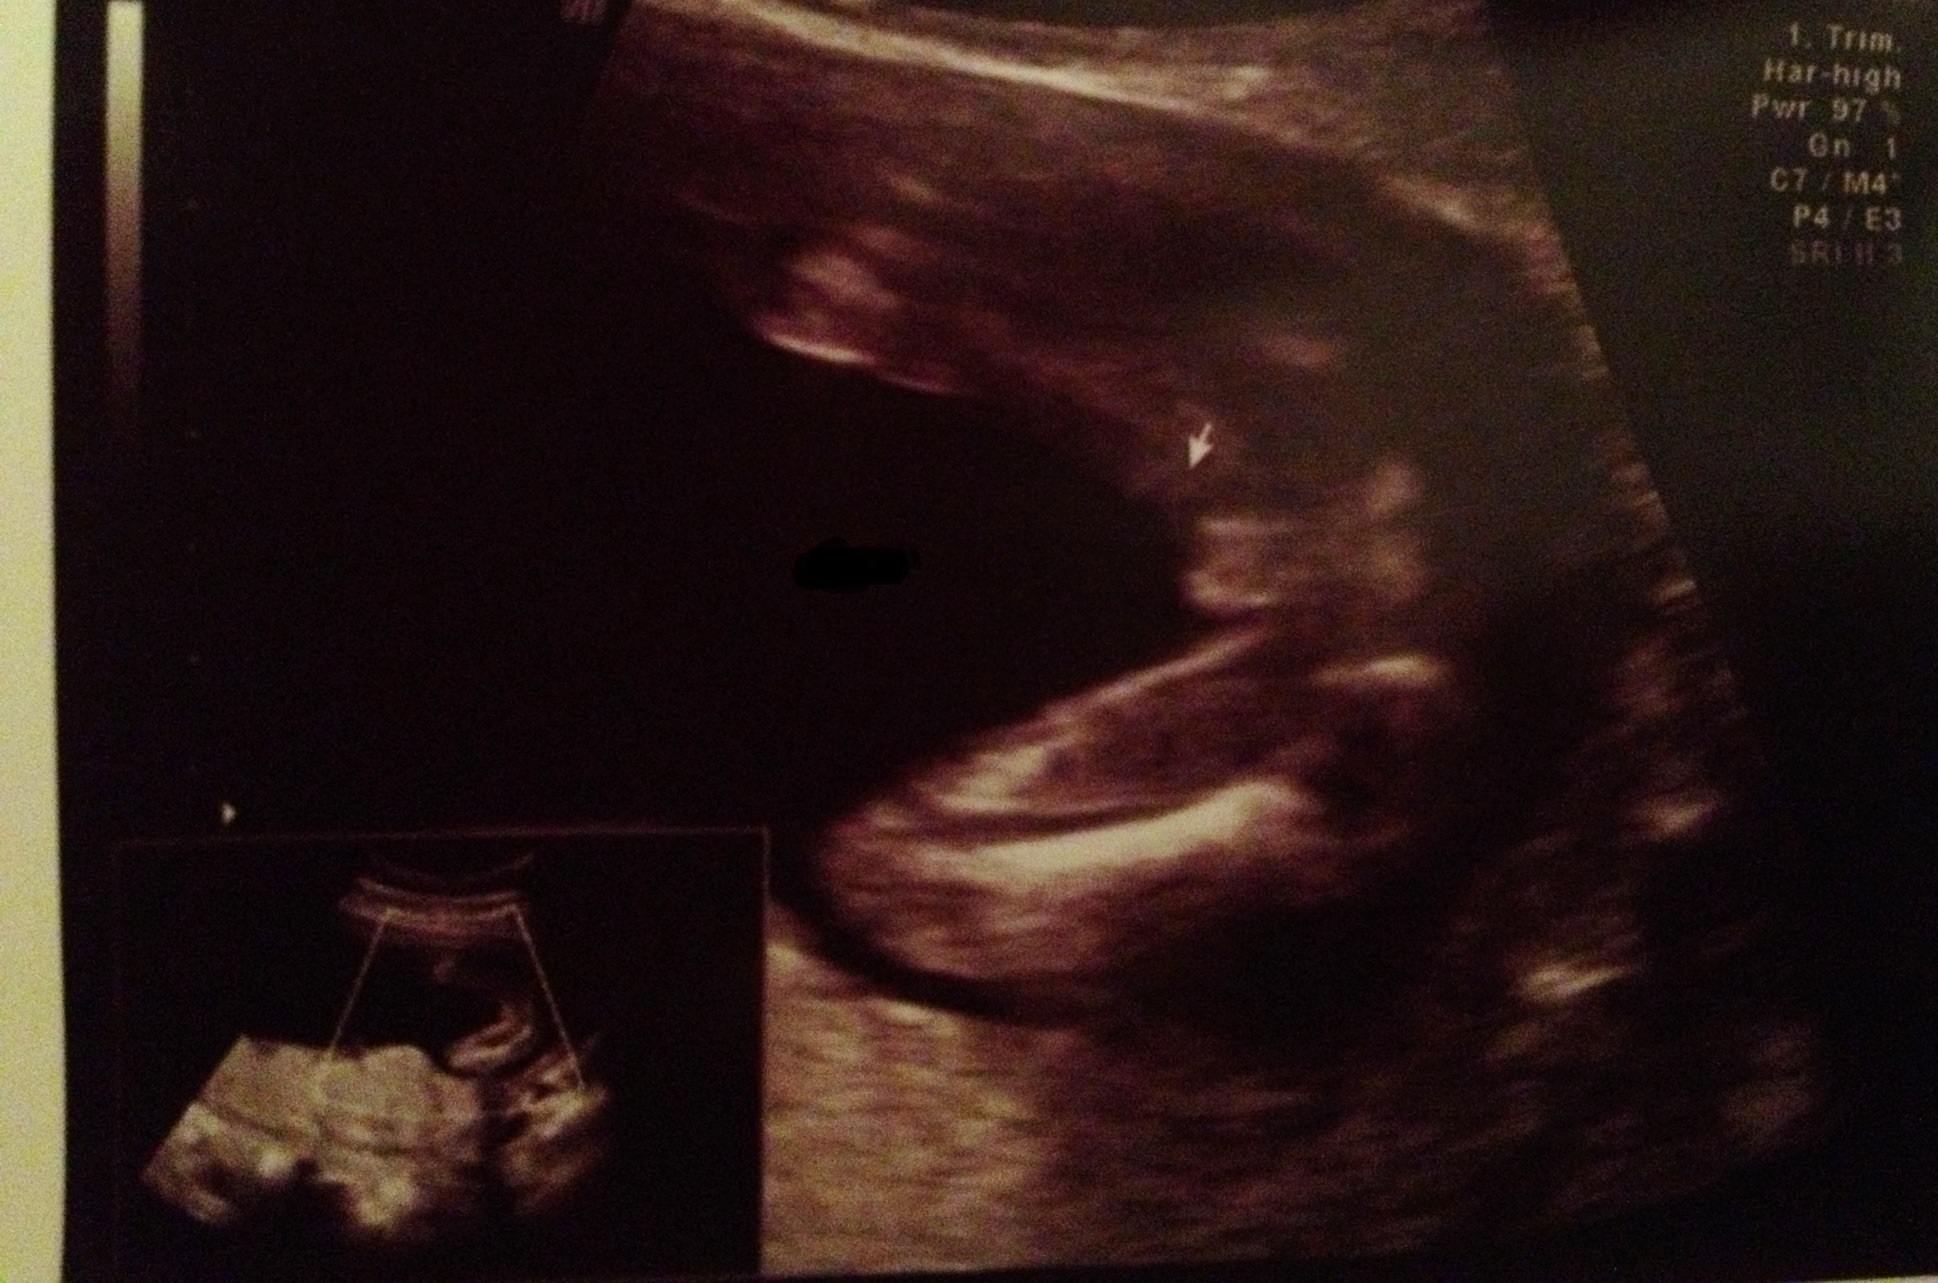

It's hard to tell.....I know the girl parts can be swollen at this point and look like boy parts. Are you finding out the gender? We aren't finding out and I am going crazy having people guess what they think we are having based on the shape of the skull! Do you have a good side profile shot of the skull you could also post?

I'd say girl! Not enough protruding to be boy for me

We are/have found out. This shot was from an elective u/s where we found out gender. I'm just curious to see what others think!

I say that's a girl. At 16 weeks I think a penis would be a lot bigger and more protruding. That just looks like swollen girl bits to me.

I say GIRL, my boys sono had obvious penis shots!

Definitely the girly 'hamburger'. Congrats!

We were told girl.